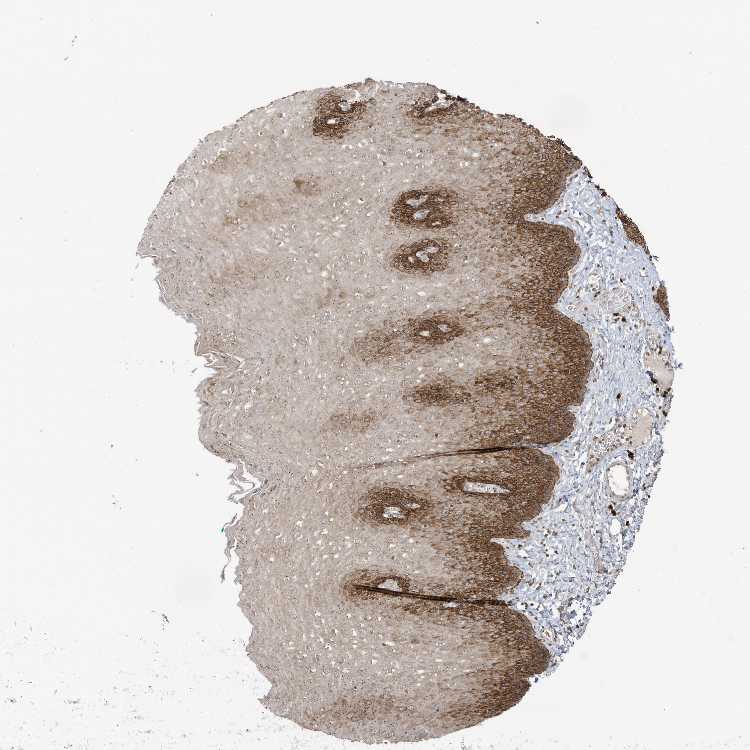

ESOPHAGUS - Antibody stainingi

Antibody staining in the annotated cell types in the current human tissue is reported as not detected, low, medium, or high, based on conventional immunohistochemistry profiling in selected tissues. This score is based on the combination of the staining intensity and fraction of stained cells.

Each image is clickable and will lead to virtual microscopy that enables deeper exploration of all samples and also displays staining intensity scores, fraction scores and subcellular localization as well as patient and tissue information for each sample.

Antibody CAB037240

Squamous epithelial cells High